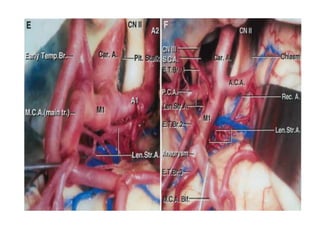

M1 segment

• Microneurosurgical and

angiographic

• Prebifurcation and post

bifurcation parts

• How to distinguish between early

branches and M1

Branching pattern M1

Early branches

• Cortical Branches from main trunk

proximal to MCA division

• types

• early temporal branches- more

common

• early frontal branches

Perforating branches

• Lenticulostraite arteries - branches of MCA that

enter anterior perforating substance (APS)

• origin from superior or posterosuperior MCA

• 3 groups : medial, intermediate and lateral

• MEDIAL: least constant, 1-5 branches from M1, enter

medial APS

• INTERMEDIATE: constant, few branches dividing,

atleast 1 major artery

• LATERAL: constant S shaped course, enter

posterolateral part of APS

M1 segment • Microneurosurgicaland angiographic • Prebifurcation and post bifurcation parts • How to distinguish between early branches and M1

Early branches • CorticalBranches from main trunk proximal to MCA division • types • early temporal branches- more common • early frontal branches

Perforating branches • Lenticulostraitearteries - branches of MCA that enter anterior perforating substance (APS) • origin from superior or posterosuperior MCA • 3 groups : medial, intermediate and lateral • MEDIAL: least constant, 1-5 branches from M1, enter medial APS • INTERMEDIATE: constant, few branches dividing, atleast 1 major artery • LATERAL: constant S shaped course, enter posterolateral part of APS

Editor's Notes

• #4 at the medial end of the sylvian fissure, lateral to the optic chiasm, below the anterior perforated substance, and posterior to the division of the olfactory tract into the medial and lateral olfactory striae